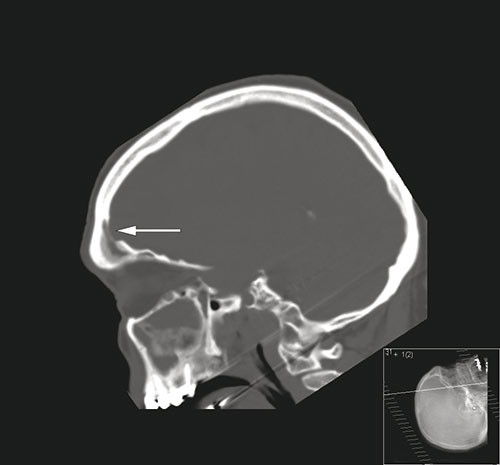

A man in his sixties was admitted to a local hospital after he was found confused and with impaired consciousness. According to informants, he had by then suffered headache for two days. On examination, he had high fever (40.5 °C), neck stiffness and a Glasgow Coma Scale score of 12. The neurological examination was otherwise unremarkable. Cerebral CT with bone window in the sagittal plane (image on the left) showed opacification of the frontal sinus and a bony defect (arrow) into the epidural space. T1-weighted contrast MRI (image on the right) showed a left-sided subdural effusion (white arrow), contrast enhancement of the dura (red arrow) and signal changes (star) in the left frontal lobe. His cerebrospinal fluid appeared turbid with a white blood cell count of 2187 · 10⁶/l (normal 0 – 5) and total protein of 1.55 g/l (normal 0.15 – 0.50). On suspicion of subdural empyema and cerebritis, the patient was provided with antibiotic therapy and transferred to the university hospital. There he underwent craniotomy and evacuation of the empyema as well as sealing of the defect in the frontal bone. Culture of the empyema revealed Streptococcus intermedius (Milleri).

Subdural empyema often presents with high fever, headache and impaired consciousness and may cause focal neurological deficits and seizures. It can be caused by the spread of bacterial sinusitis through erosion of bone barriers to the epidural space (1). Cerebral MRI enables visualisation of cerebral infections with a high degree of sensitivity (2) and it is essential that patients with a demonstrated empyema or abscess are promptly referred for surgical drainage (1).